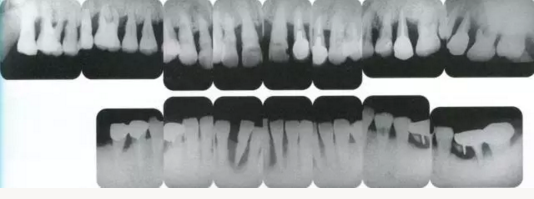

333333.png

▲圖19-14

佩戴最終修復(fù)體時(shí)的X光片。骨邊緣水平平坦,探診值維持在1~2mm。